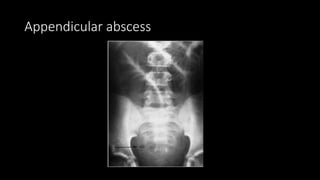

Appendicular abscess